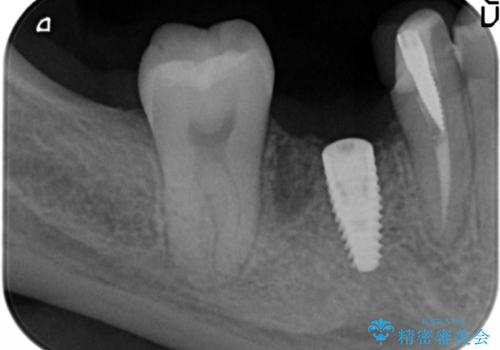

インプラント治療をご希望されたため、植立を行いました。

インプラントを入れる際、部分的に骨を増やす処置を行っています。